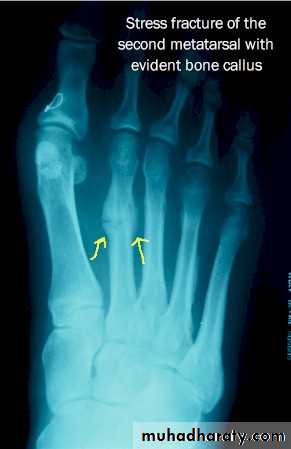

These fractures occur in Normal bone which is subject to repeated stress, typically seen in athletes or military personnel.

This is most seen in tibia, fibula and metatarsal.

The great difference between stress and traumatic fractures is that there is no single specific injury in case of fatigue fractures, the onset of pain is gradual and increase by activity and relieved by rest.

Examination reveals local tenderness over the affected bone. X-ray finding may be normal at first time and after 2-4 weeks the radiological changes appear as a faint hairline crack surrounded by callus, occasionally if a biopsy taken from the callus may be mistaken to diagnosed as a bone sarcoma!!!!). A mistake that should not occur if the feature of stress fracture are properly understood.

Treatment: rest + non-steroidal anti inflammatory drugs